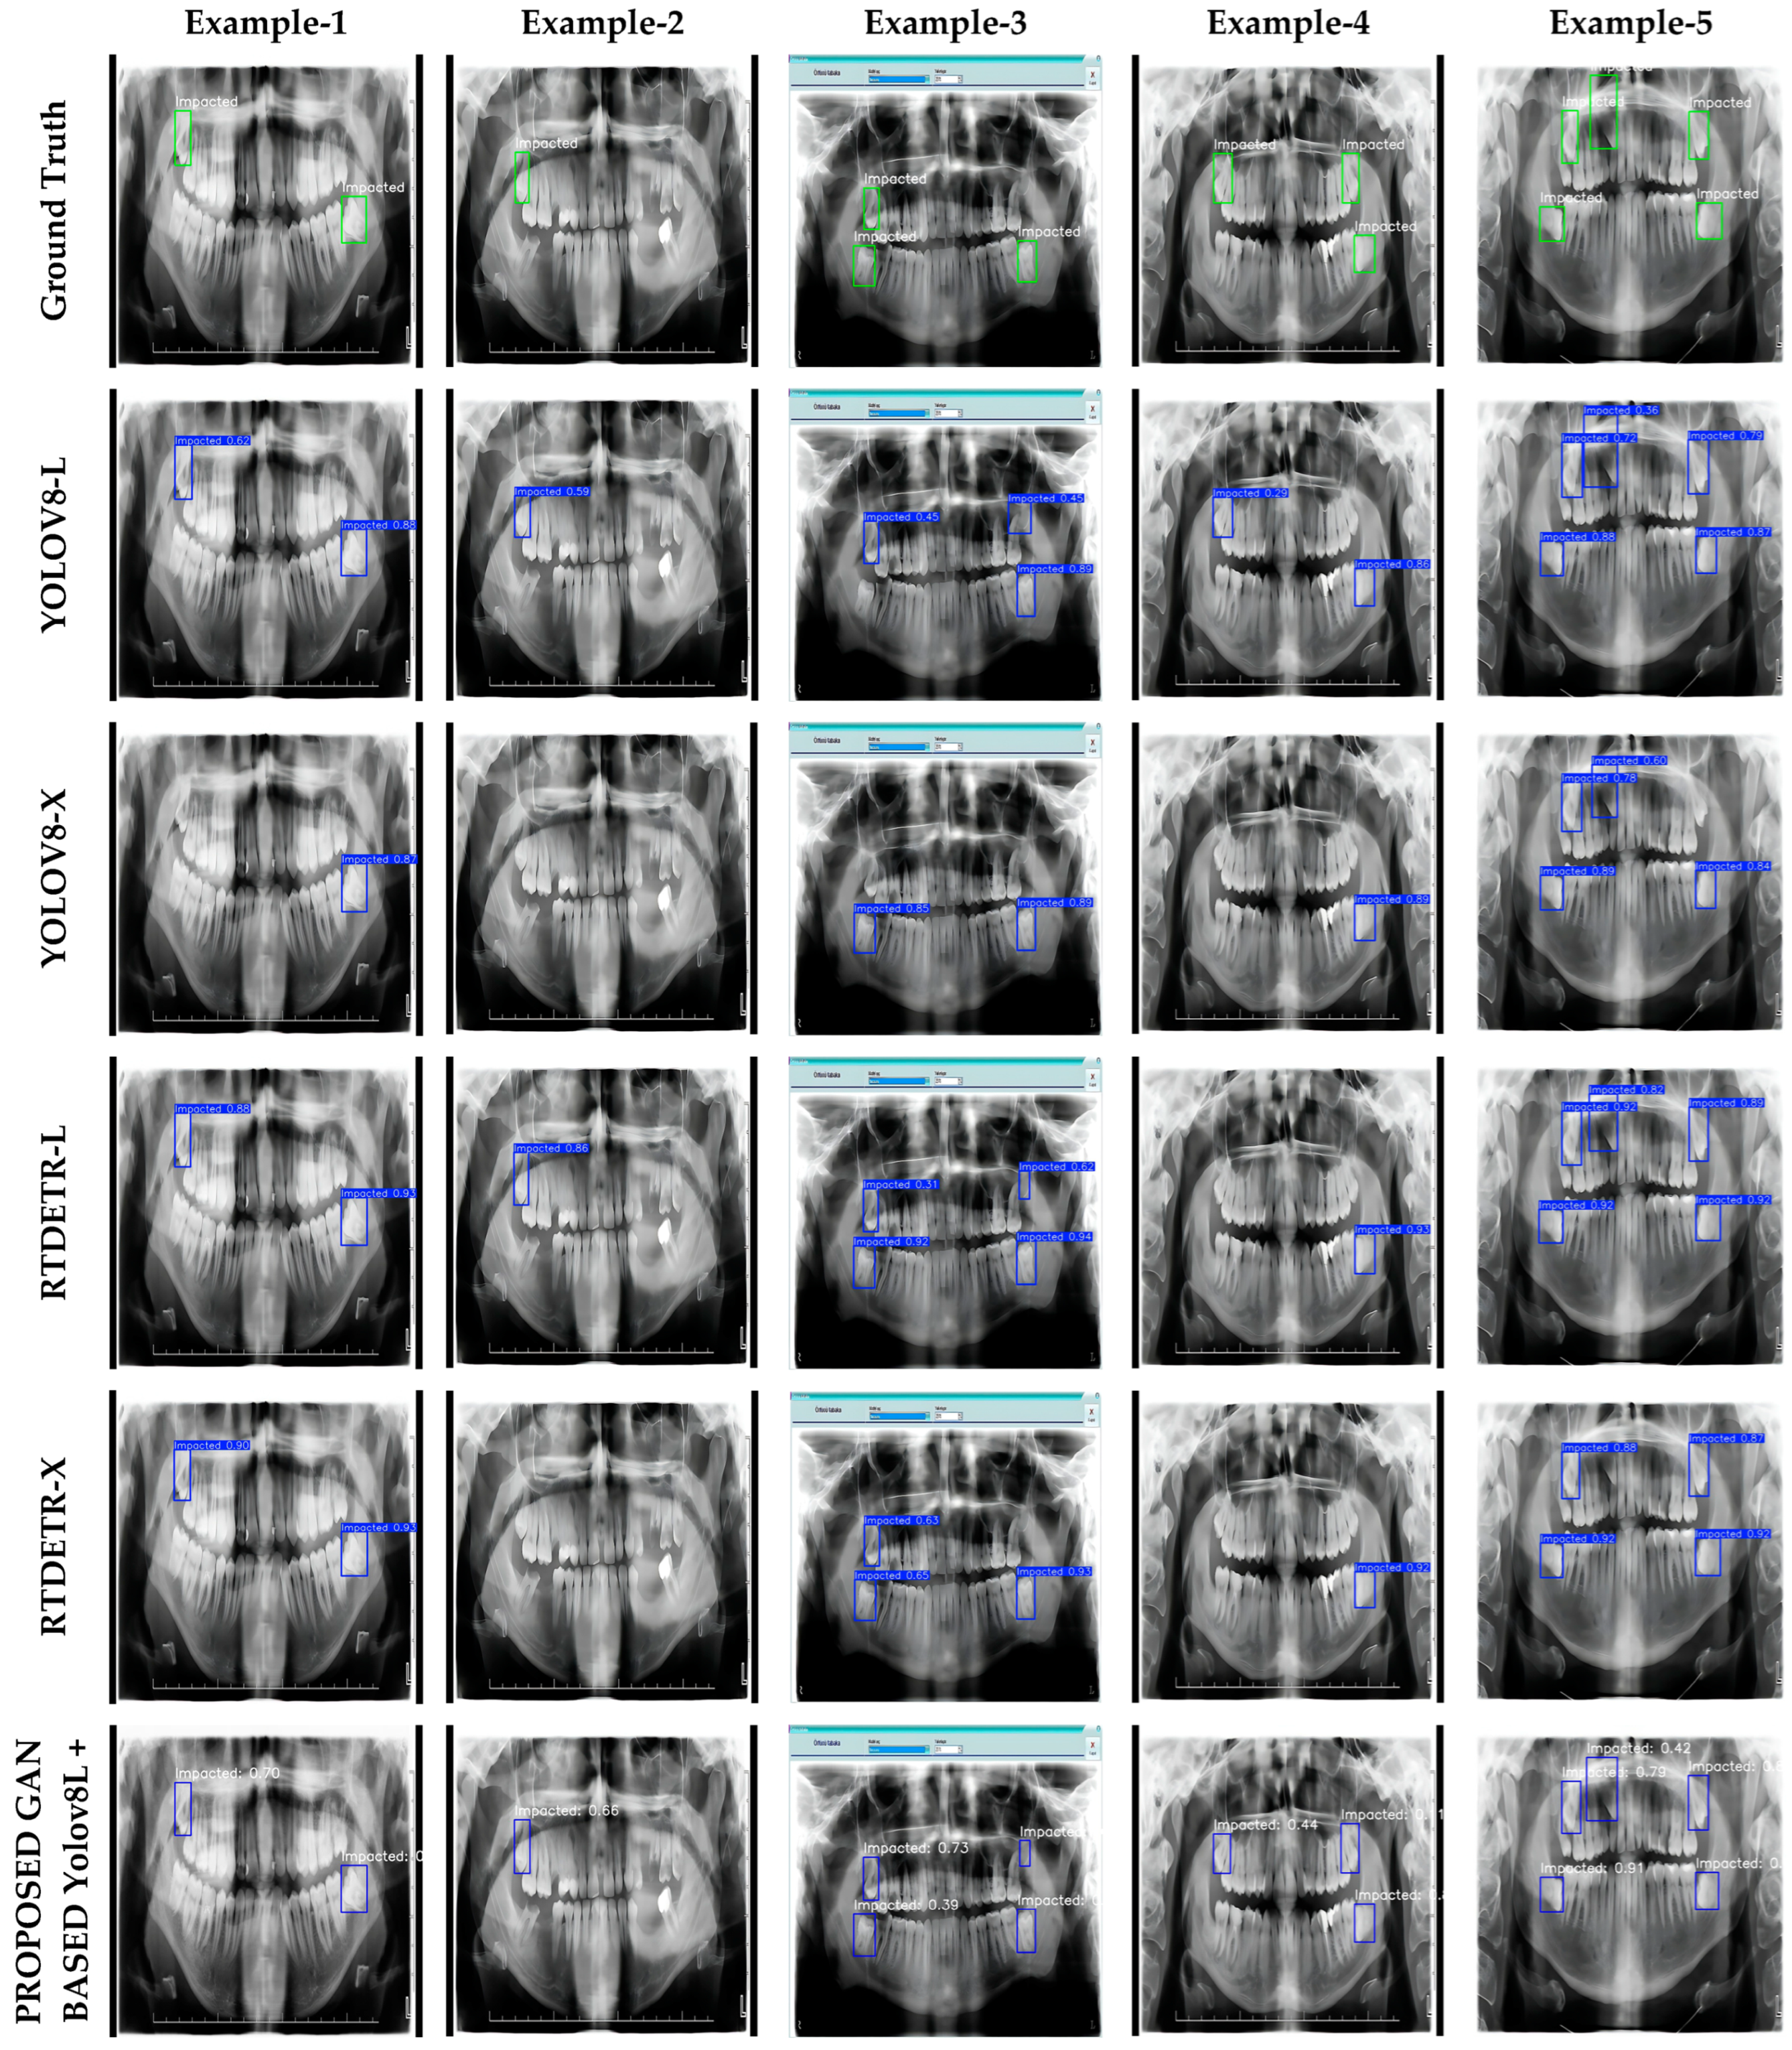

3.4. Visualization